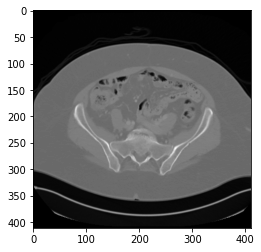

mask = morphology.dilation(mask, np.ones((1, 1, 1)))这将产生以下图像:

正如你所看到的,在上面的图像中,CT扫描也是扭曲的。

如果我将:mask = morphology.dilation(mask, np.ones((40, 40, 40)))更改为mask = morphology.dilation(mask, np.ones((100, 100, 100))),则生成的映像如下: